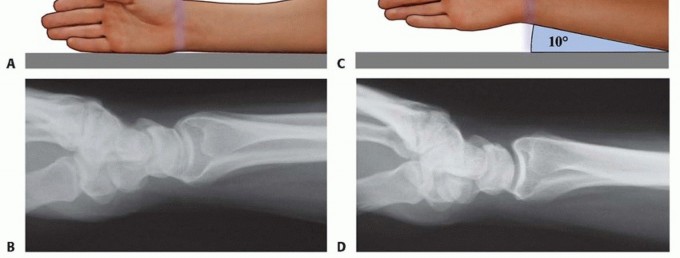

FIG 2 • Articular fracture components.

Structurally, the wrist can be thought of in terms of three basic support columns: a radial column that includes the radial border of the distal radius and scaphoid facet, a middle column consisting of the central and ulnar part of the radial shaft and lunate facet, and an ulnar column that includes the DRUJ, the triangular fibrocartilage complex (TFCC), and the ulnar head.The radial column fragment involves the pillar of bone along the radial border of the distal radius ( FIG 2). Restoration of radial length is important to correct the axial position of the carpus, unloading deforming compressive forces that can interfere with reduction of middle column injuries. Typically, the terminal portion of the brachioradialis inserts on the base of the radial column fragment and may be a deforming force that contributes to proximal displacement of the radial column fragment. Metaphyseal comminution along the base of the radial column fragment may also contribute to radial column instability. Although not common, radial column injuries with secondary coronal fracture page or segmental comminution into the shaft proximally can be particularly unstable fracture patterns.The volar rim of the lunate facet is a primary load-bearing structure of the articular surface. Instability of the volar rim occurs in two patterns:In the volar instability pattern, the volar rim migrates in a proximal and volar direction resulting in secondary palmar translation of the carpus.In the axial instability pattern of the volar rim, axial impaction of the carpus drives the volar rim into dorsiflexion, resulting in secondary axial and dorsal subluxation of the carpus.The ulnar corner fragment involves the dorsal half of the sigmoid notch and usually includes a small dorsal ulnar corner of the articular surface of the lunate facet. This fracture component is the result of impaction of the lunate into the articular surface, causing the fragment to migrate dorsally and shorten proximally. Residual displacement of the ulnar corner may result in instability of the DRUJ as well as restriction of forearm rotation.Dorsal wall fragmentation may be a typical finding in either dorsal bending or axial loading injuries. If displaced, this fracture component is often associated with dorsal subluxation of the carpus in addition to the typical dorsal angulation of the articular surface.Free articular fragments may be impacted within the metaphyseal cavity and result in incongruity of the articular surface. Elevation of dorsal wall fragments allows direct access to reduction of free articular fragments.